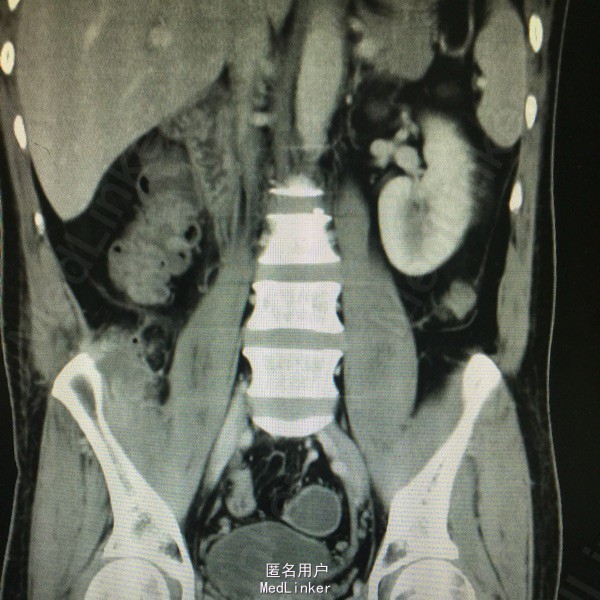

男,41岁,反复右侧腰部疼痛3。患者3月前出现右腰部疼痛,伴低热,就诊当地医院,超声提示腰大肌脓肿,给予穿刺引流,抗感染治疗。同时活检病理无特殊。现疼痛来我院。

局部皮肤完整,右侧腹部肌紧张,压痛明显,反跳痛阳性。

行脓肿切开引流术,术中见 牙签一枚!术后一周拔除引流管,复查脓腔缩小,无发热无疼痛。

患者不明原因导致牙签滞留体内,反复发热疼痛,影像检查未发现,排除结核感染。及时手术是最佳治疗。